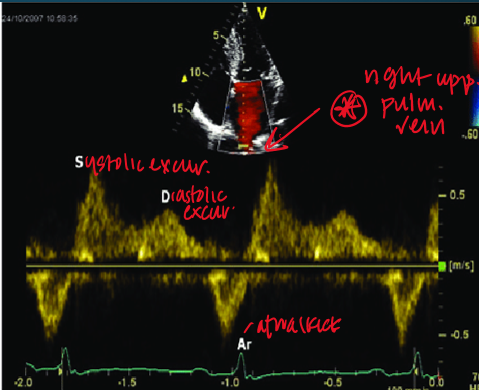

how do you obtain pulmonary venous flow? (view, doppler, cursor)

in 4CH view you can see paralel alignment with right superior pulmonary vein

pulsed wave doppler

1-2cm from orifice

what clinical measurements are done with pulmonary venous flow?

peak systolic velocity (PVs)

peak diastolic velocity (PVd)

peak atrial reversal velocity (Pva)

duration of pulm vein atrial reversal (a-dur)